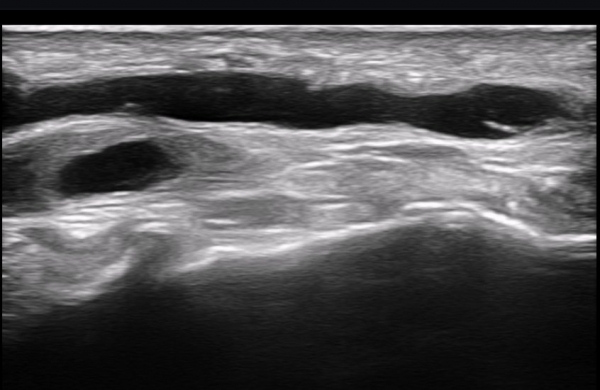

ÃÊÀ½ÆÄ ¼Ò°ß : ºñº¹½Å°æ Ⱦ´Ü¸é°Ë»ç¿¡¼­(»çÁø 1~13) ºñº¹½Å°æÀÇ Àú¿¡ÄÚ ºÎÁ¾°ú ´Üºñ°ñ°Ç³» ³¶Á¾¼º º´º¯ÀÌ °üÂûµÈ´Ù.

ºñº¹½Å°æ Á¾´Ü¸é°Ë»ç(»çÁø 14, 15)¿¡¼­ ºñº¹½Å°æÀÇ Àü¹ÝÀûÀÎ Àú¿¡ÄÚ ºÎÁ¾°ú ºñº¹½Å°æ ½ÉÃþÀ¸·Î ´Üºñ°ñ°Ç³»

³¶Á¾¼º º¯º¯ÀÌ °üÂûµÈ´Ù.